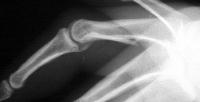

Xrays show a complex intraarticular fracture of the proximal phalanx head. There is a displaced spiral oblique longitudinal fracture with a second oblique coronal split through the articular surface of the radial condyle.

Palmar displacement of a portion of one condyle is visible on the lateral view.